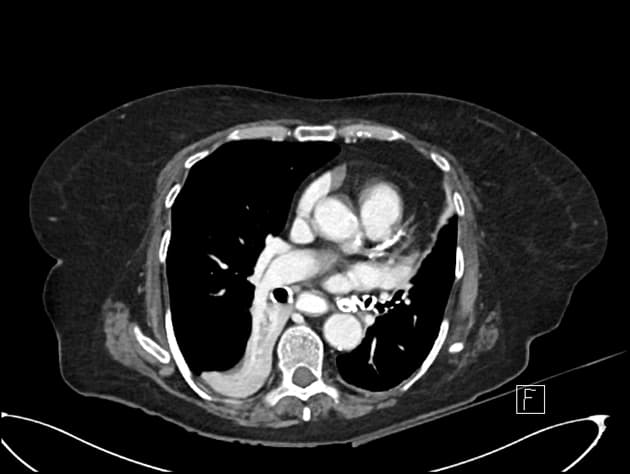

Axial C+ portal venous phase

Chấn thương gan - độ IV theo phân loại AAST

- Ghi nhận một vết rách gan kèm theo huyết khối trong nhu mô gan, ảnh hưởng đến các phân đoạn IV, V và VIII theo phân loại Couinaud, kích thước khoảng 82 x 65 x 82 mm, có điểm chảy máu hoạt động (active bleeding site) bên trong.

- "Sự hiện diện của chảy máu hoạt động trên CT có cản quang cho thấy tổn thương nguy cơ cao, cần theo dõi sát hoặc can thiệp."

Hình ảnh học phù hợp với tổn thương gan độ IV theo phân loại AAST, có chảy máu hoạt động (active hemorrhage), kèm theo tổn thương thận phải độ I.